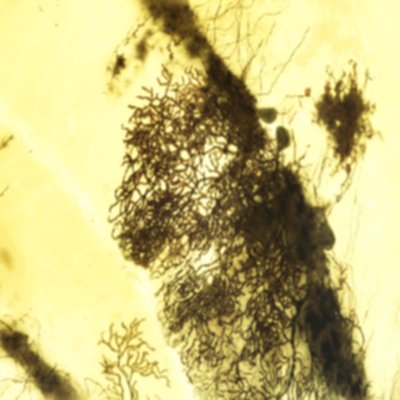

Plexos